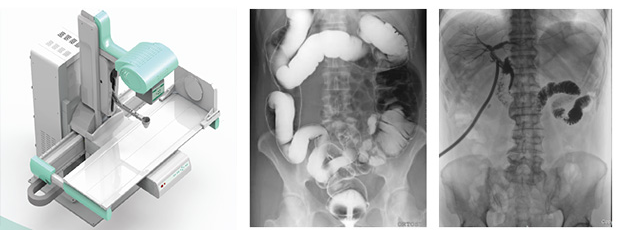

只需一塊動(dòng)態(tài)平板探測(cè)器,即可高效輕松實(shí)現(xiàn)攝影、透視和造影功能,幾乎可以滿足醫(yī)院全科室的臨床檢查需求。

17*17英寸的高清像素動(dòng)態(tài)平板探測(cè)器,能對(duì)胸部、腹部等部位實(shí)現(xiàn)大范圍全覆蓋,動(dòng)靜態(tài)之間無感切換。透視檢查無須對(duì)患者重新定位便可觀察到足夠大的人體器官組織,避免漏診誤診。更好地減少了曝光時(shí)間,也減少了病人的輻射劑量。

大尺寸動(dòng)態(tài)平板技術(shù),覆蓋檢查面積范圍廣,輕松實(shí)現(xiàn)胃十二指腸等大面積造影,無需移動(dòng)即可觀看整個(gè)動(dòng)態(tài)過程,避免噪點(diǎn)對(duì)圖像的影響。

2)圖像質(zhì)量無畸變,無失真

高效動(dòng)態(tài)平板技術(shù),圖像不會(huì)有幾何畸變,提供高分辨率和精確的圖像,為臨床診斷提供精準(zhǔn)依據(jù)。